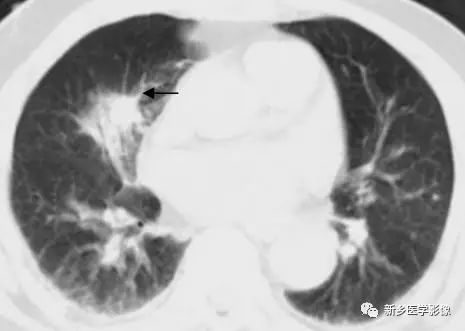

胸部CT肺窗图:显示毛刺征(↑示)

指自肿块边缘向周围呈放射状分布的线状影。粗短毛刺常提示其为恶性,是肿瘤细胞沿周围结构浸润性生长所致。慢性炎性病变多表现为长毛刺,是结缔组织反应性增生的一种表现。

③.毛刺征